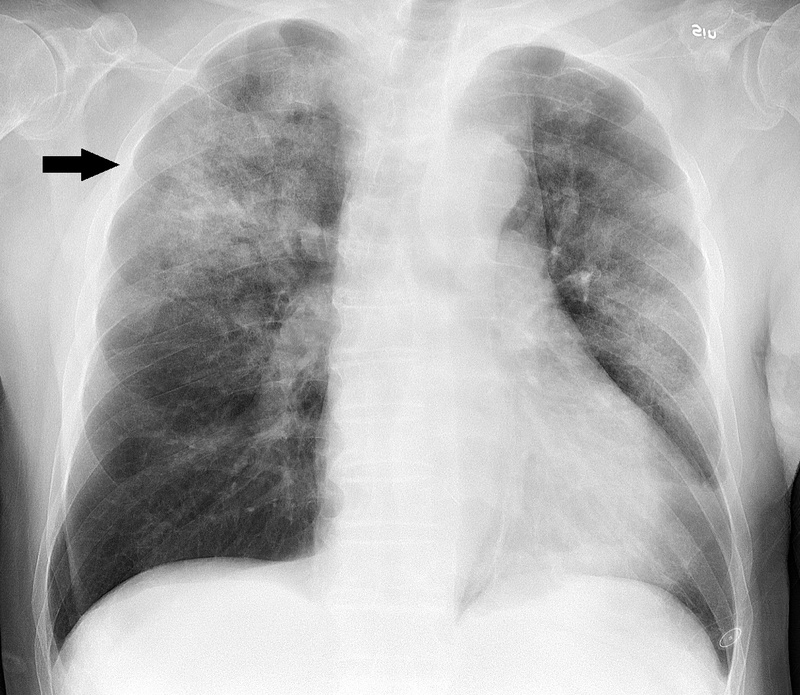

Viêm phổi có thể khó chẩn đoán do có một số triệu chứng tương tự như cảm lạnh hoặc cúm. Do đó bác sĩ sẽ yêu cầu các xét nghiệm khác nhau để chẩn đoán viêm phổi, chẳng hạn như: